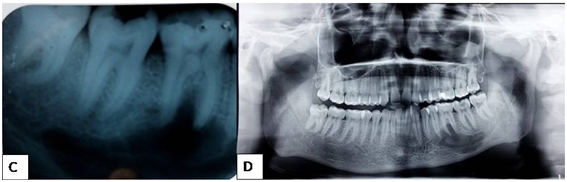

Figure 3 E- showing axial section of a CBCT image showing no cortical expansion. F- 3D section of the same showing horizontal bone loss and no cortcal expansion.